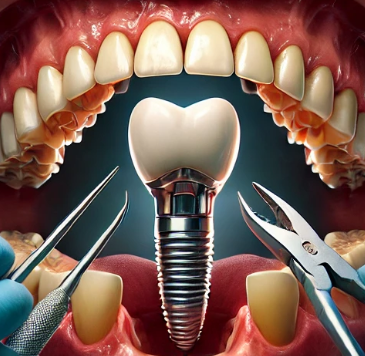

2. 임플란트 식립

임플란트 식립 단계에서는 티타늄으로 된 인공 치근을 잇몸 속에 심습니다. 티타늄은 인체에 잘 맞고, 시간이 지나면서 뼈와 융합되므로 안정적입니다. 이 과정은 국소마취로 이루어지며, 환자는 통증을 거의 느끼지 않습니다. 임플란트를 심고 나면 몇 달 동안 뼈와 임플란트가 잘 융합되도록 기다리는 기간이 필요합니다. 일반적으로 이 기간은 3개월에서 6개월 정도가 소요됩니다.

3. 임플란트 지대주 부착

뼈와 임플란트가 안정적으로 융합된 후, 지대주라는 작은 부품을 임플란트에 부착합니다. 이 지대주는 인공 치아와 임플란트를 연결하는 역할을 하며, 이후 인공 치아가 올바르게 장착될 수 있도록 도와줍니다.

4. 인공 치아 장착

마지막으로, 인공 치아를 제작하여 지대주 위에 장착합니다. 이 인공 치아는 환자의 치아 모양과 색상에 맞춰 맞춤 제작되며, 자연스러운 외관과 편안한 착용감을 제공합니다. 이렇게 완성된 어금니 임플란트는 자연치와 동일한 기능을 수행하게 됩니다.